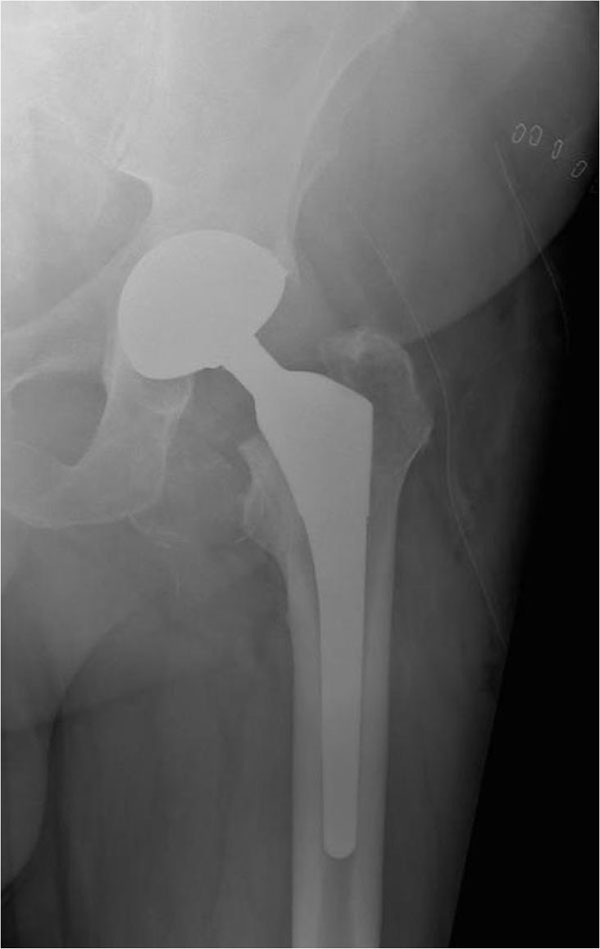

Hip replacement implant installed in the pelvis bone. Medically Stock Steel Hip Replacement standard total hip replacement (thr) designs provide excellent analgesic relief and predictable outcome, with a. a traditional hip replacement implant uses a metal femoral head (the ball of the implant) and conventional. anyone who has had an depuy asr or asr xl hip replacement and has any outstanding questions should contact the asr helpline. Hip replacement implants. Steel Hip Replacement.